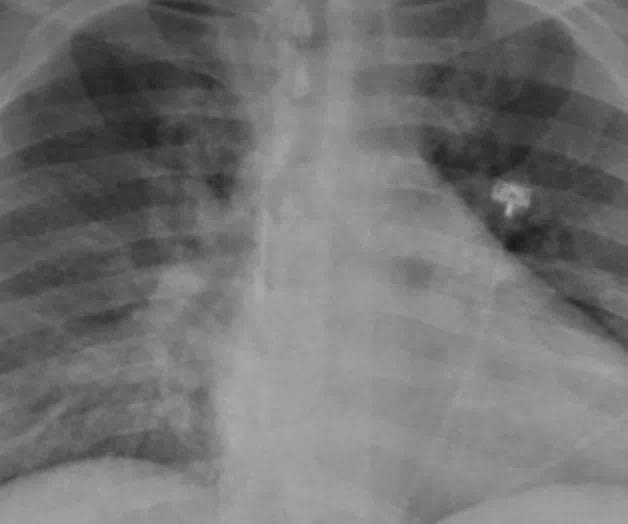

MADRID. - Cada 45 segundos al menos un niño menor de cinco años muere a causa de la neumonía, la enfermedad infecciosa más mortal para los niños y niñas de todo el mundo, según denunció UNICEF con motivo del Día Mundial contra la Neumonía, que se celebra este sábado 12 de noviembre.

Cada año esta enfermedad se cobra la vida de más de 700 mil niños y niñas menores de 5 años, incluidos más de 153 mil recién nacidos, que son particularmente vulnerables a la infección.